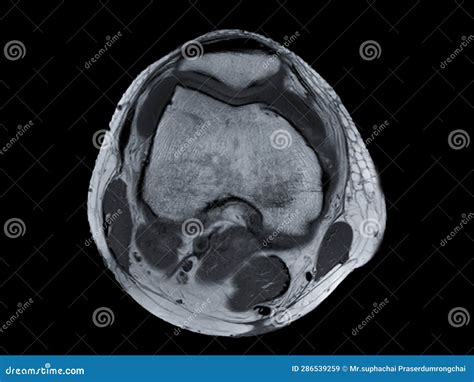

• Positioning: You will lie down on a padded table. The technician will position your knee within a specialized device called a "coil," which helps capture clear images of the joint. The table will then slide into the cylindrical MRI scanner.

• The Scan: It is crucial that you remain completely still during the scan, as movement can cause the images to become blurry, making them difficult for radiologists to interpret.